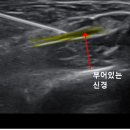

• 요골 | 홍콩여행가서 요골신경마비 걸린 사람의 후기

에스컬레이터가 있고 건물 내부가 넓지 않아 접근하기 편했음! ​ ​ 주의. 요골신경마비 검사할 땐 하루 일정을 그냥 비워두는 편이 좋습니다 ​ 10시 10분 내원 후...덕분에 다이아를 찍었습니다 우와 ㅋㅋ 자랑이당! ​ ​ 초음파 검사 후기 초음파 검사해주신 의사 선생님 존함은 기억 안 나지만 정말 친절하시고 꼼꼼하게 잘...

레츠 자서전(2025-10-12 23:34:00)